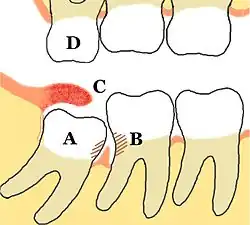

Impacted wisdom teeth are classified by the direction and depth of impaction, the amount of available space for tooth eruption and the amount of soft tissue or bone that covers them. The classification structure allows clinicians to estimate the probabilities of impaction, infections and complications associated with wisdom teeth removal.[31] Wisdom teeth are also classified by the presence of symptoms and disease.[32]